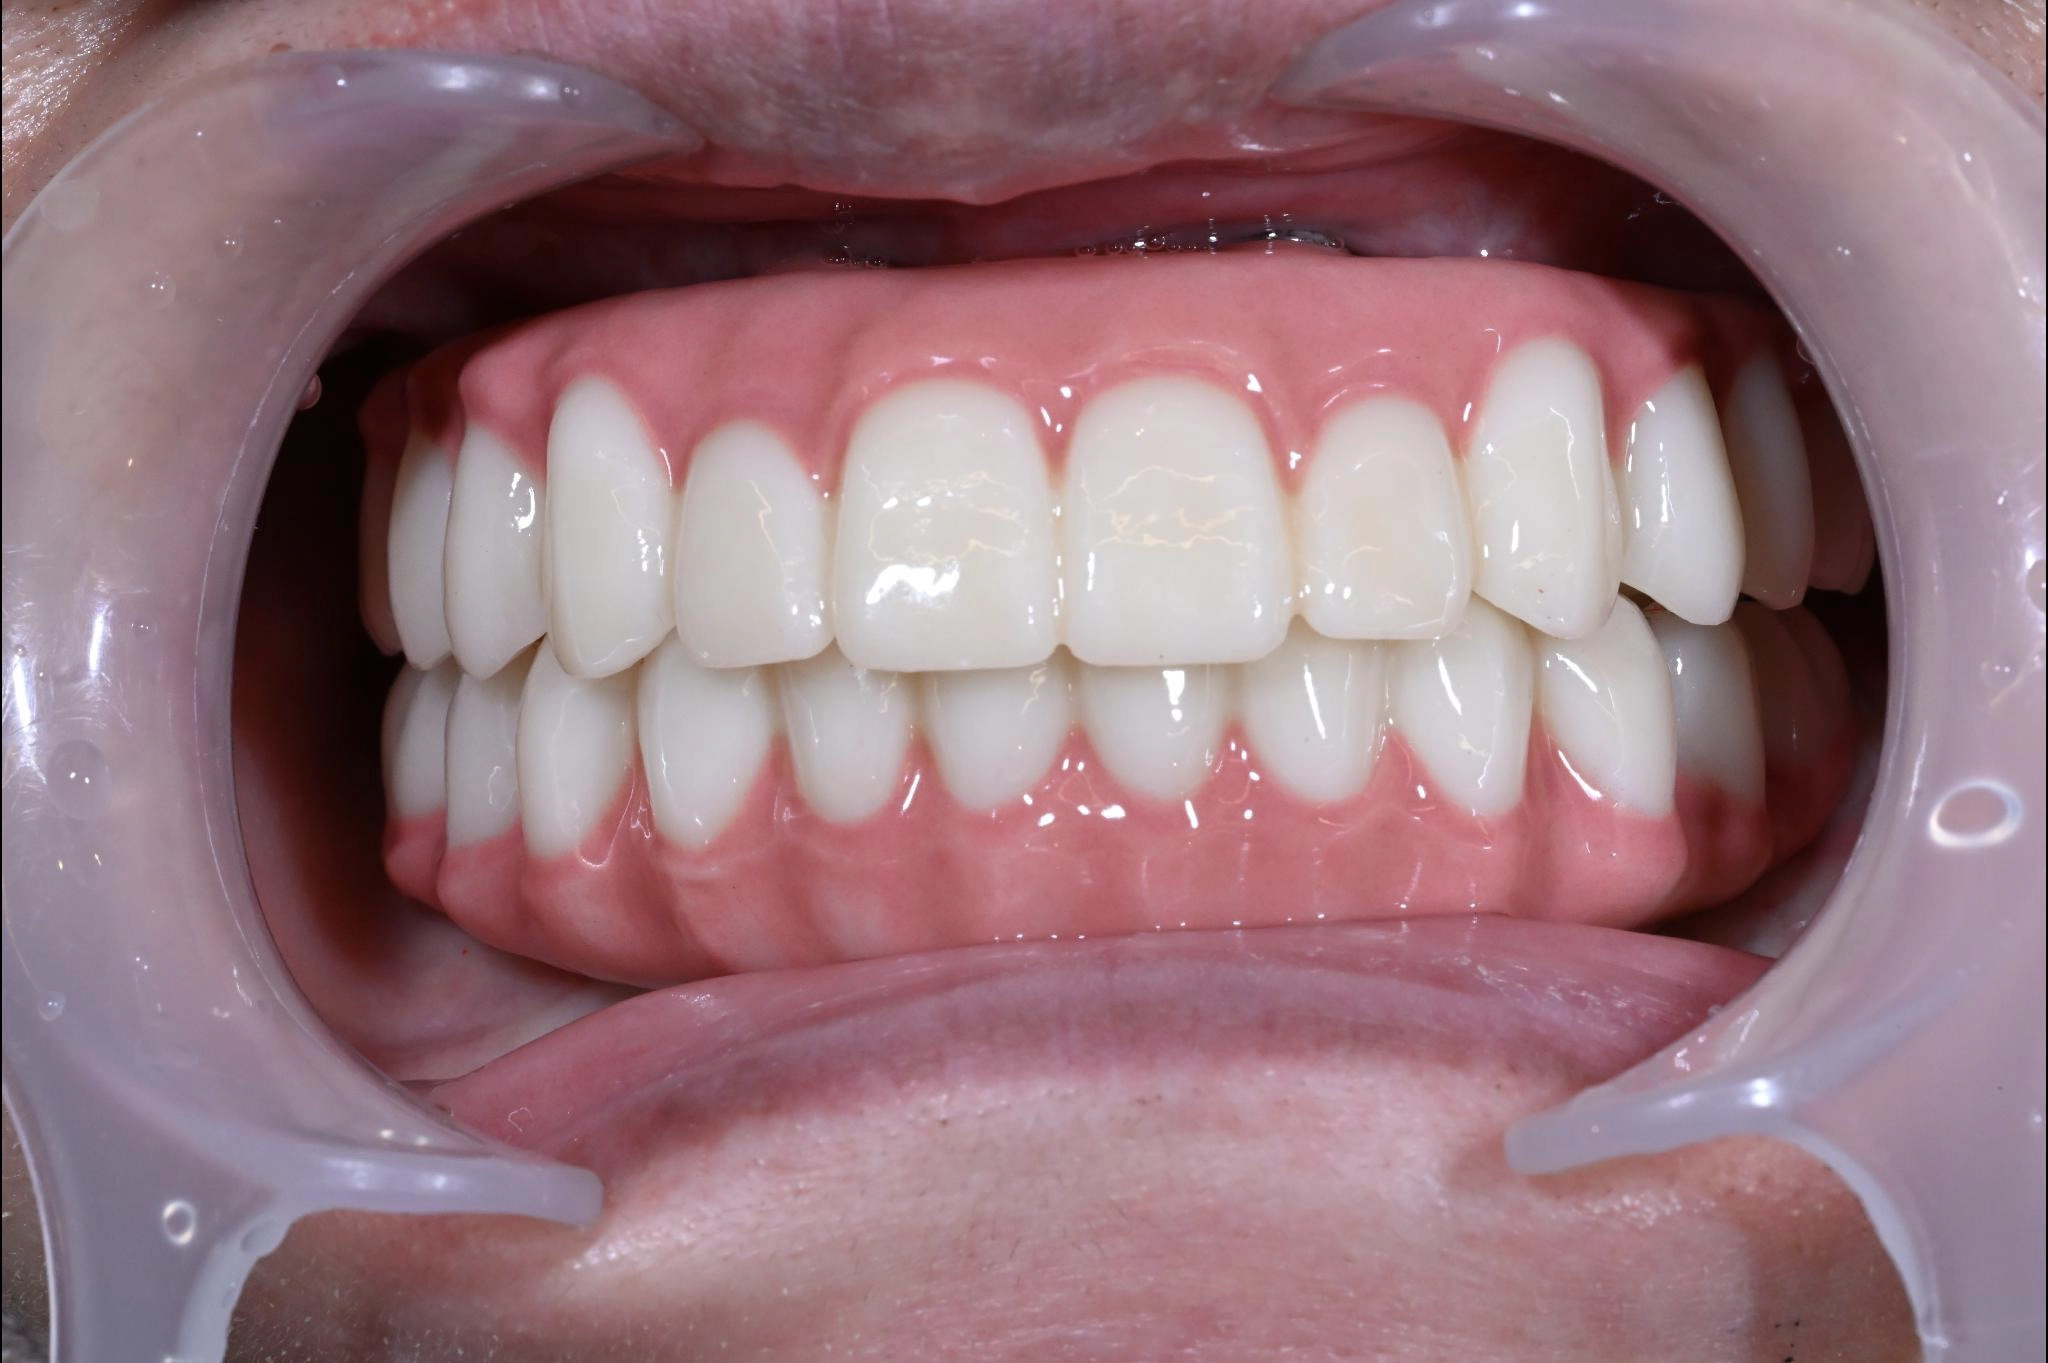

大分県 45歳(女性)

「マスクを外して人付き合いをしたい」

術前

術後

内容 :上下顎オールオン4ザイゴマ0

費用 :4,365,900円

※モニター価格

期間 :半年

リスク:出血・腫れ・痺れ・痛み

「何度も通って恥ずかしい思いを長引かせたくない」という気持ちがありましたので、治療期間が短く、たった1日で固定式の歯が入ることがとても魅力的でした。

手術に対しては強い恐怖心を持っていましたが、実際には術中の記憶はほとんどなく、痛みを感じることもなく無事に終えることができました。

これまでは口元を気にして人との接触を避けていましたが、「笑顔で話したい」という明るい気持ちになれました。